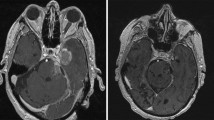

VMAT has also opened the door for single-isocenter treatment of multiple brain metastases in a single radiotherapy session of 30–40 min. Historically, the treatment of each metastasis required a separate isocenter, and subsequently, the repositioning of the patient which in turn required confirmation using image-guidance; thus, treatment of multiple metastases could take hours, resulting in a clinical burden for resource utilization and patient comfort. Through VMAT, multiple lesions can now be treated with a single isocenter in a matter of minutes (Fig. 2) [21]. One minor drawback of VMAT is that there is a higher amount of scatter radiation, but it is minimal and clinically insignificant (Fig. 3).

Planning view of reconstructed head in a thermoplastic SRS mask as part of a VMAT single-isocenter multi-metastases brain plan. Right-sided (orange in online version) and left-sided (blue in online version) arrows represent the 0- and 180-degree arcs of VMAT; other arcs at 30-, 60-, 90, 120-, and 150- degrees, are represented by the thin lines. This patient had metastatic adenocarcinoma of the lung with 9 brain metastases, all treated with a single-isocenter VMAT plan. Each individual lesion was < 2 cm and received 21 Gy in a single fraction. Isodose line figures can be seen in Fig. 3. (Color figure online)

Isodose line distributions (key at far right, color-coded version online) of a single-isocenter multi-metastases VMAT plan, with axial, sagittal, and coronal views. Nine metastases were treated simultaneously, but not all lesions are in view. The outermost (light blue in online version) isodose line represents 525 cGy, the amount of radiation that “spills” in the normal adjacent brain. (Color figure online)